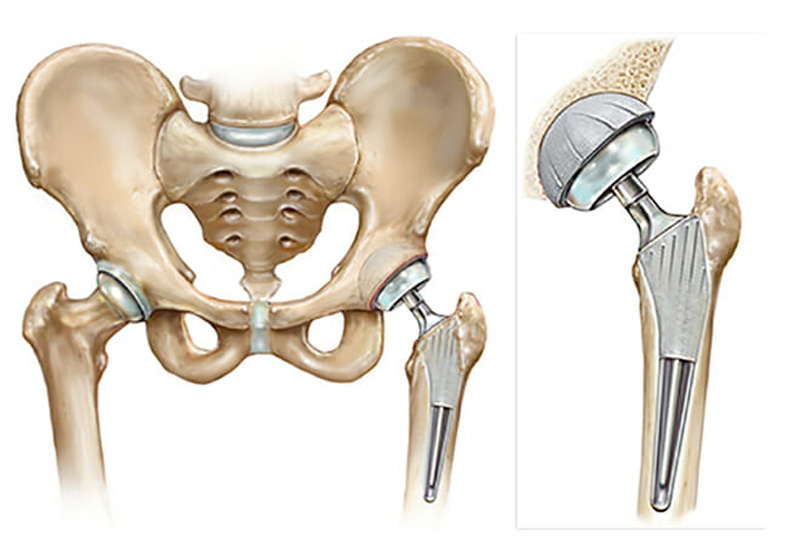

Эндопротезирование тазобедренного сустава: фото и схемы